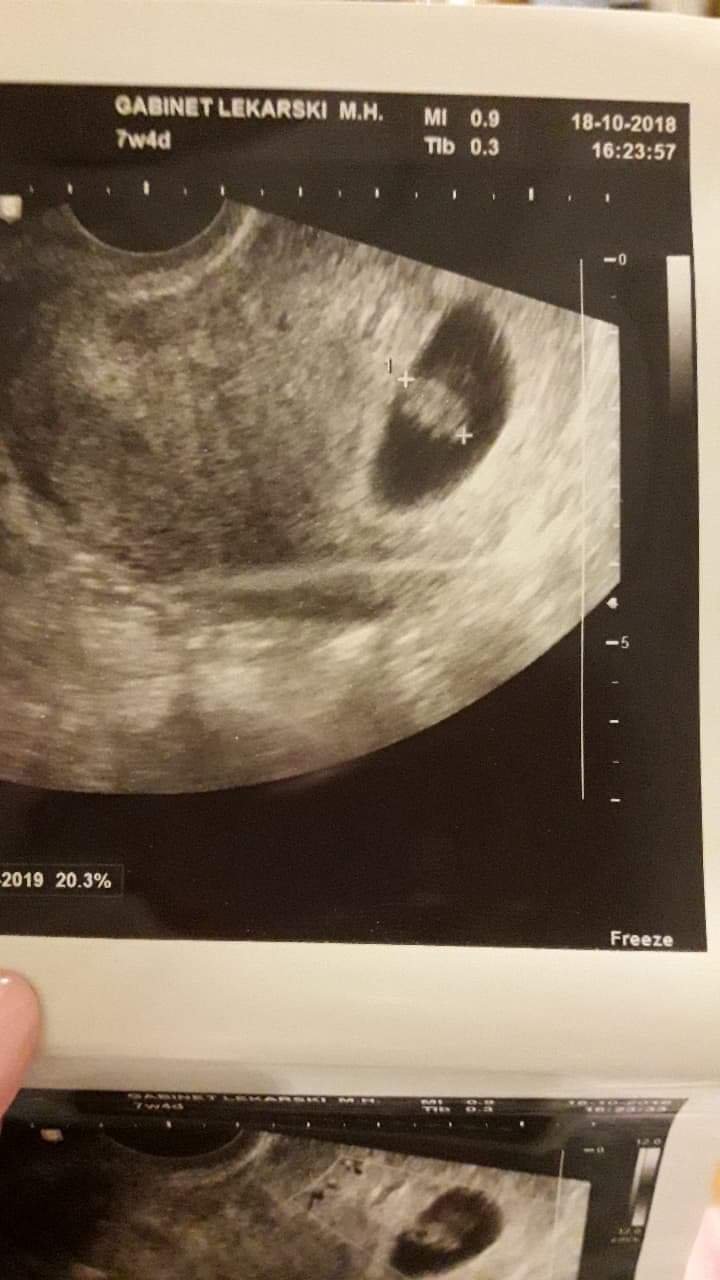

Dziewczyny ja jestem po wizycie. Mój dzidziuś ma caly 1 cm[emoji16] termin z om 2.06 z usg 5.06

Maleństwo ma 7mm, pięknie bijące serduszko i wiek płodu wychodzi 6t4d (wg OM 7 t) także to będzie do zweryfikowania na następnej wizycie.

Niesamowite przeżycie! Cieszę się szalenie! :) :) :) Zobacz załącznik 908810Zobacz załącznik 908811Zobacz załącznik 908812